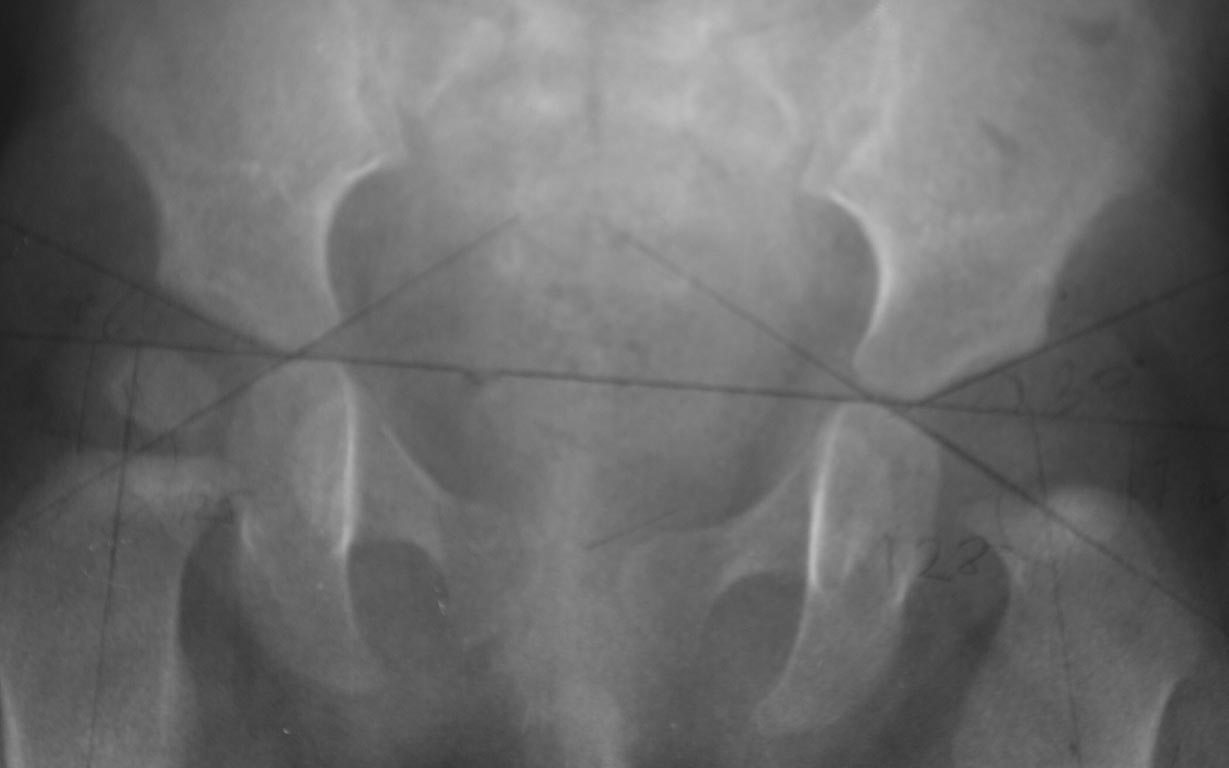

Добрый вечер уважаемые коллеги. Помогите советом, в какую клинику и к

кому обратится с данной проблемой( у ребенка в возрасте 1мес.

диагностирован гематогенный остеомиелит головки бедра). Лечили

консервативно( выписку и фото в динамике прилагаю). На сегодняшний день

ребенку 11 мес. Детские ортопеды по месту сомневаются в тактике( в плане

операции или выжидательная тактика). Хотелось проконсультироваться с

теми кто занимается этой проблемой. Заранее спасибо.